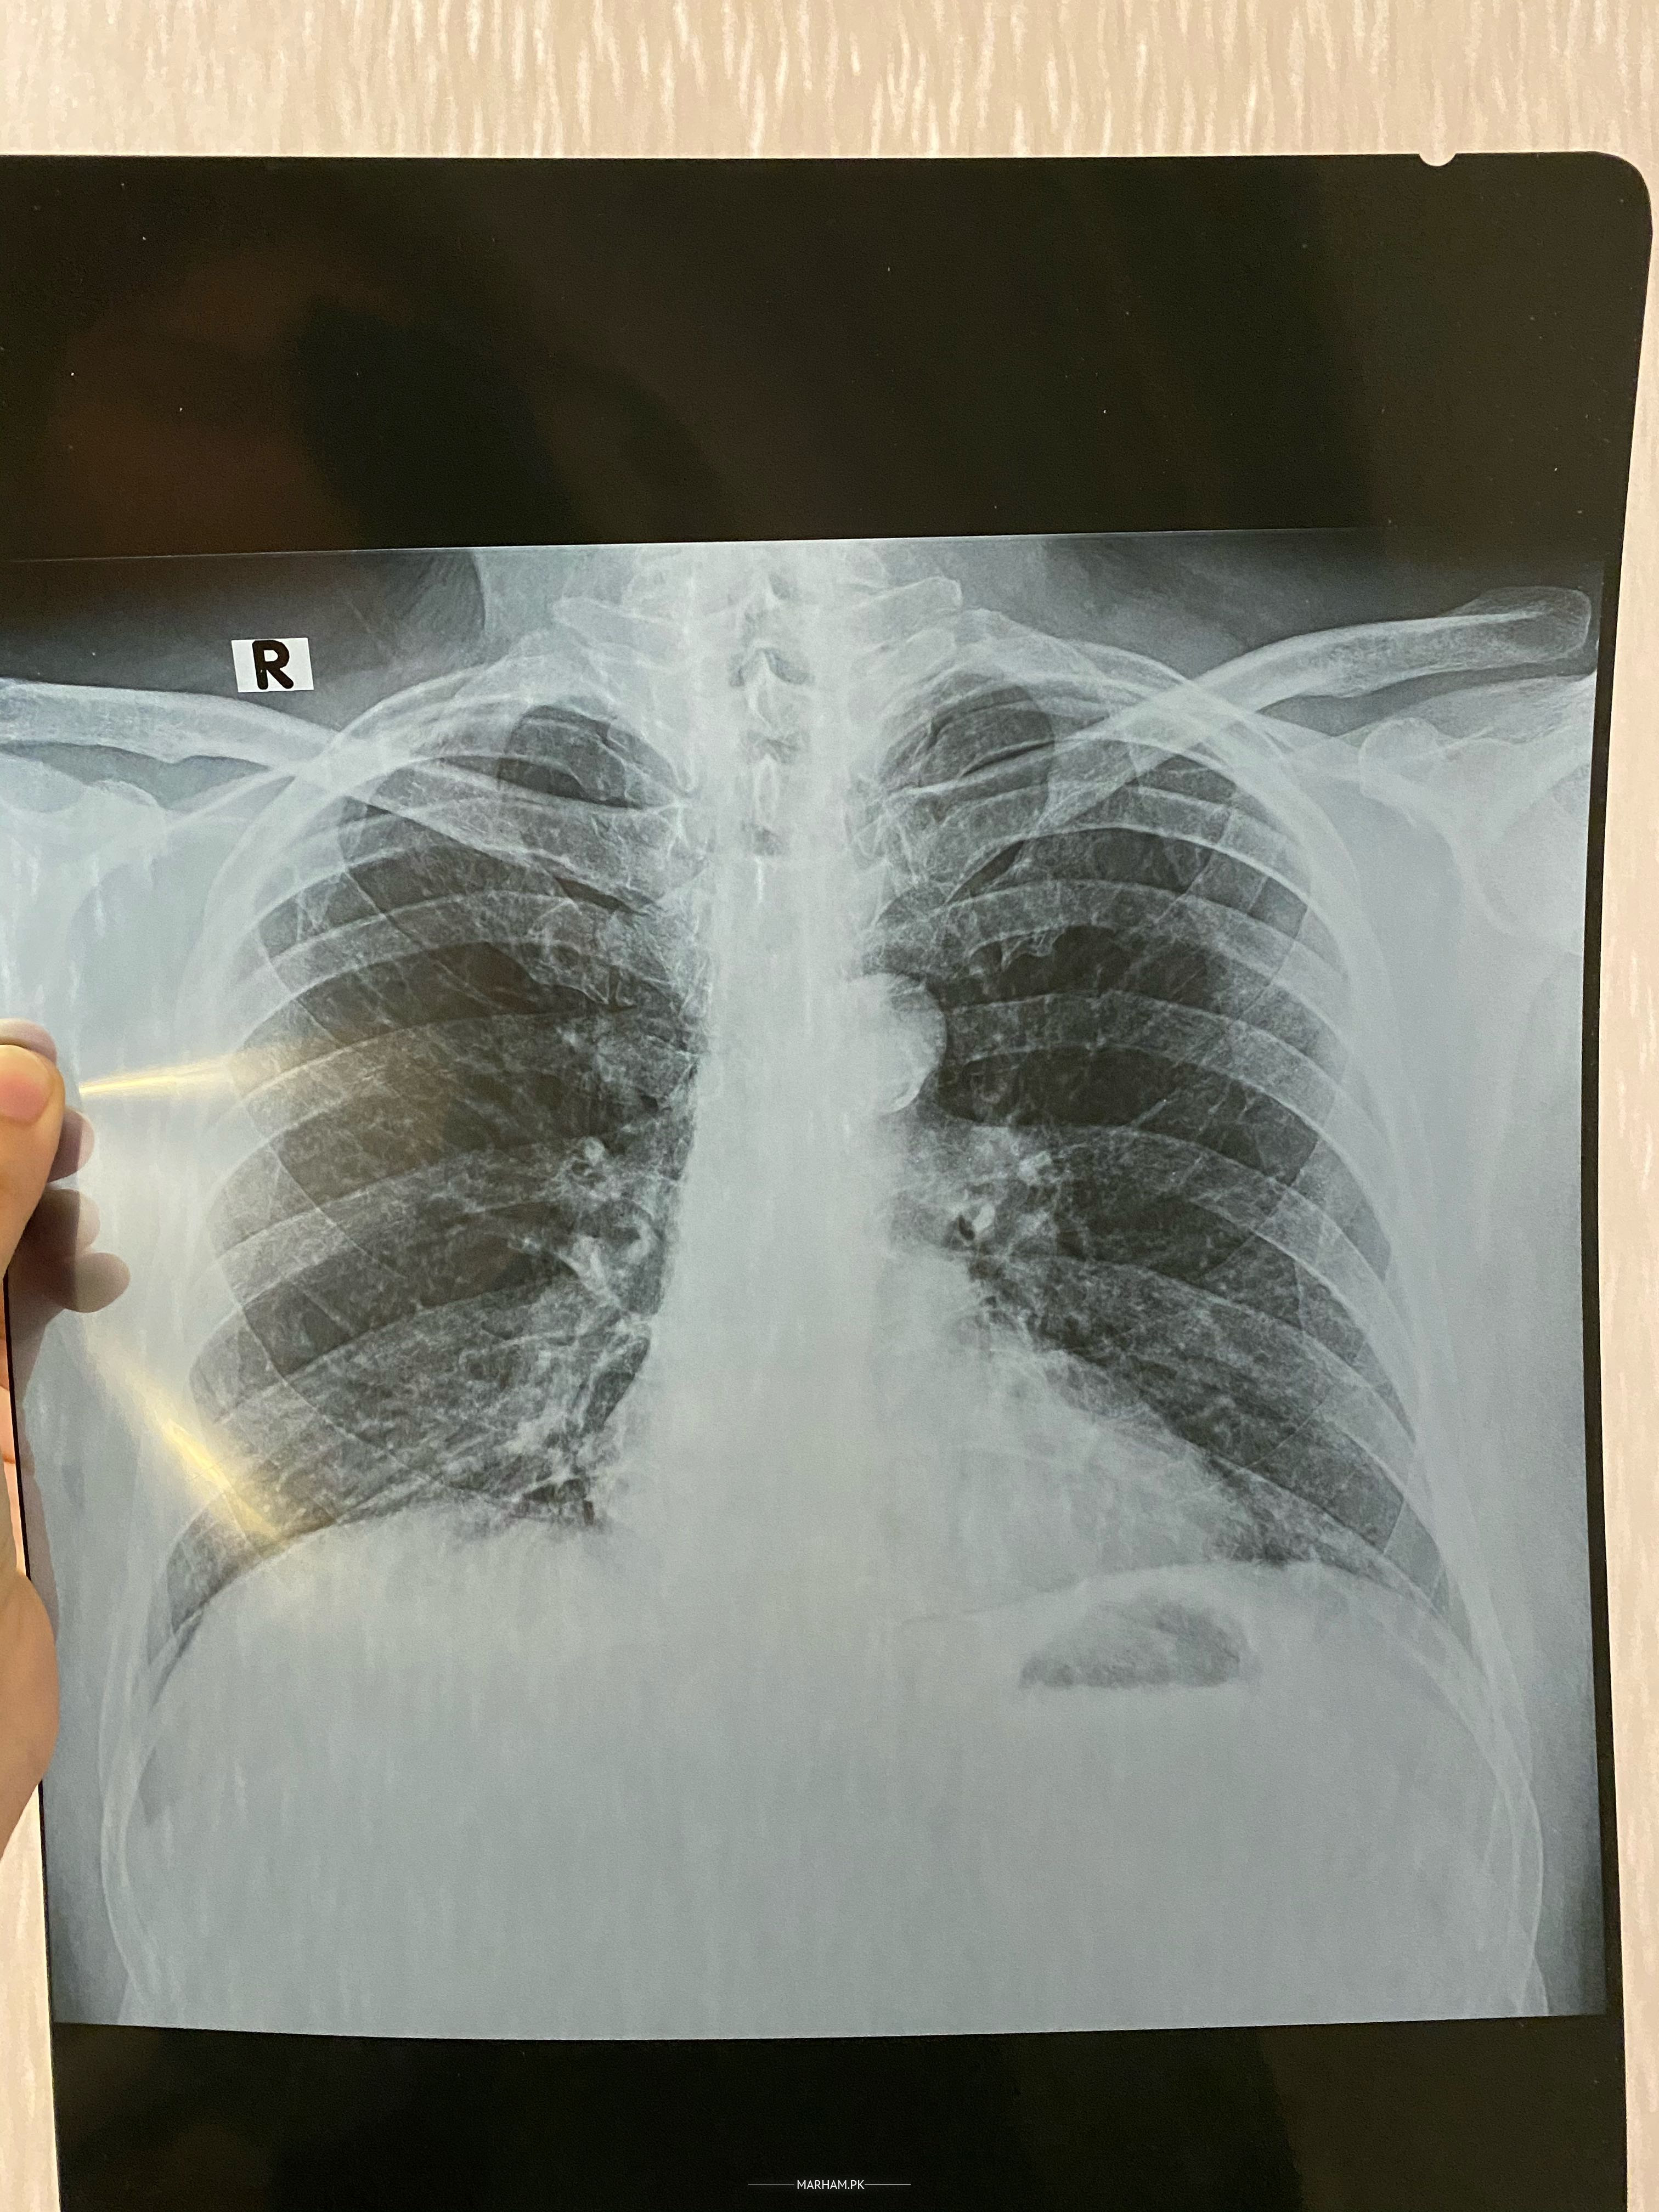

Asking For Someone else, Father, Male, 62 Years old, Pakistan

My father just returned home from overseas travel and has been coughing. A doctor said he might have typhoid and he took cough syrups and medicines and soon felt better. However, he has started coughing again. He is a heart patient and has got stent in 2017. He is also taking his heart medications. This is his report as he has been coughing a lot. Its sometimes dry and sometimes with phlegm. Please let me know what the reports indicate. He does not have coronavirus as he’s already already tested for it twice.

Xray is not bad. So far it is not suggestive of corona.

If cough persists for a week or he has increased difficulty in breathing, get a checkup and corona pcr

tab Avelox 500 od for 7 days